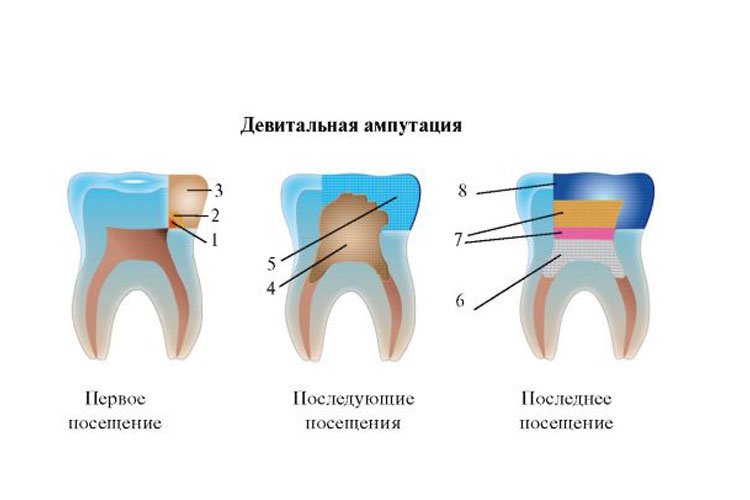

Культя зуба это

Культя зуба это 106 фото